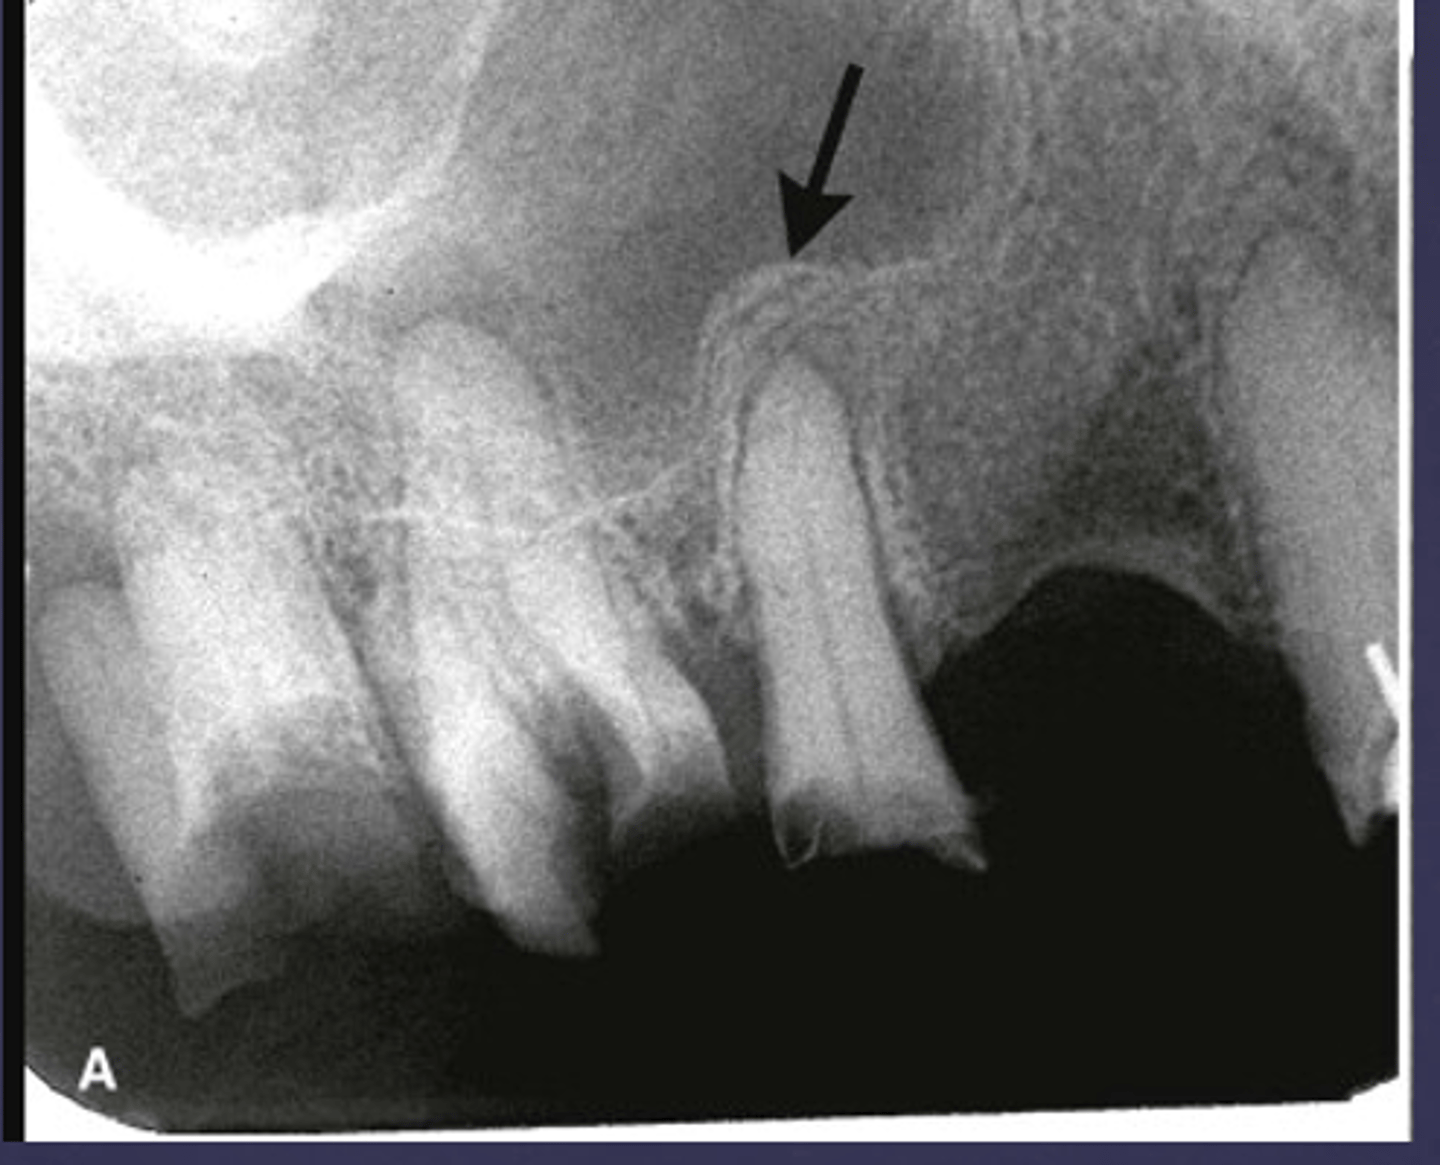

What is the black arrow pointing at?

sequestrae

What is the white arrow pointing at?

periosteal reaction

periosteal reaction (increased bone density)

sequestra

What phase of osteomyelitis does this show?

acute (multiple sequestrae)